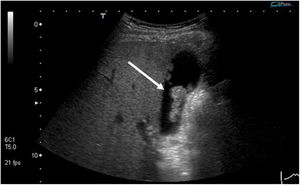

| Adenoma | Risk of malignant degeneration; may be sessile or pedunculated.Most frequent histologies: tubular, papillary or tubulopapillary | Homogenous on ultrasound, with echogenicity similar to the liver (Fig. 3). |